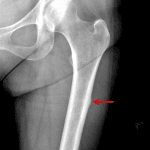

- Focal cortical thickening along the lateral aspect of the subtrochanteric left femur

- Atypical femoral fracture (Insufficiency fracture of the lateral subtrochanteric left femur)

Focal cortical thickening along the lateral aspect of the subtrochanteric left femur, consistent with atypical femoral fracture which can be seen with chronic bisphosphonate use.